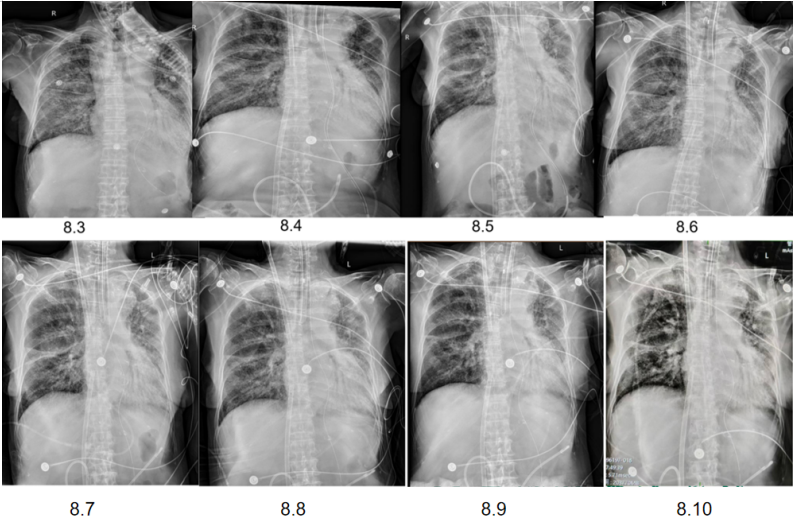

经过上述治疗,患者WBC、CRP、LDH、PCT均逐渐下降,肌酐正常。8月10日检查:WBC 9.1×109/L,CRP 6.8 mg/L,PCT 0.04 ng/ml,LDH 406 U/L。8月3-10日期间,患者心率持续变快,需要两种血管活性药物控制血压,无法进行俯卧位通气。ECMO上机前,患者右肺渗出性病变明显加重(图3)。

图3 患者床旁胸片变化情况

8月11日呼吸机吸氧浓度40%,ECMO气浓度约为80%,持续3天,激素减量氧合恶化,因心脏问题不能俯卧位通气(心率快,应用艾司洛尔及胺碘酮控制心室率)。气道分泌物不多,炎症指标正常。心脏问题,快速性心律失常,请心内科专家会诊,考虑舒张功能障碍,建议盐酸地尔硫卓联合胺碘酮控制心室率,血压低考虑可能血管张力问题,为减轻去甲肾上腺素对心脏的刺激,调整间羟胺维持血压。6月26日用抗肿瘤靶向药物后,8月1日肺部CT,双肺病变明显加重,肿瘤进展还是感染诱发?或是肿瘤靶向药物引起的免疫相关性肺损伤?下一步怎么办?肿瘤靶向药物还能用吗?8月11日请詹庆元教授会诊,考虑肿瘤靶向药物引起间质性肺炎可能性大,甲强龙80 mg q12h;心内科建议倍他乐克6.25 mg q12h口服联合盐酸地尔硫卓控制心室率;间羟胺替换去甲肾上腺素。8月12日心率65~85次/分,俯卧位8小时,白天ECMO 80%下调60%。患者氧合持续好转,随着病情好转,抗生素降阶梯治疗。8月13日,BALF涂片发现大量白细胞,以及多种形态阴性杆菌,像洋葱伯克霍尔德菌和伊丽莎白菌。8月14日,tNGS结果回报按蚊伊丽莎白菌、洋葱伯克霍尔德菌和脓肿分枝杆菌。据此调整抗感染药物:磺胺2片tid,多黏菌素E,美罗培南,利奈唑胺,伏立康唑。8月20日撤离ECMO。8月21日,病原学提示脓肿分枝杆菌进行性增多,加用左氧氟沙星。8月26-28日尝试甲强龙减量(60 mg→40 mg),患者再次再次出现氧合变化,未能成功转换为无创通气,有创通气PS降至8 cmH2O,PEEP 5 cmH2O。复查胸部CT,发现右肺渗出性病变再次出现。8月29-30日,甲强龙剂量调整为80 mg。8月31至9月3日,甲强龙剂量调整为60 mg。8月27日复测tNGS,回报木糖氧化无色杆菌(序列数47605),人类疱疹病毒1型(序列数176998),按蚊伊丽莎白菌、洋葱伯克霍尔德菌和脓肿分枝杆菌序列数较前减少。细菌室回报木糖氧化无色杆菌。患者出现了一些不良反应,包括骨髓抑制,纤维蛋白原、血小板、血红蛋白、白细胞、淋巴细胞数都在降低。考虑可能是磺胺药物和利奈唑胺引起,所以停用这两种药物。调整抗感染药物:阿米卡星雾化,左氧氟沙星,多西环素,伏立康唑,阿昔洛韦。之后由于不良反应,8月31日停用了左氧氟沙星和多西环素。9月3日查血,患者血小板升高。如下图所示,6月15日为抗肿瘤药物使用前,8月1日为抗肿瘤药物使用后,8月19日第一次复查CT,激素减量后,8月29日再次复查CT,右肺渗出性病变较前明显增多(图4)。